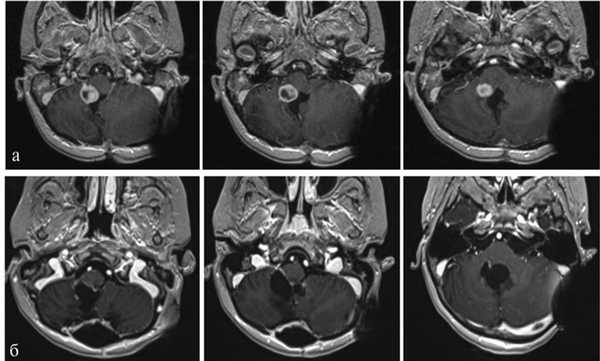

Пациентка Д., 4 года. Госпитализирована в институт 15.09.14. Диагноз: рецидив анапластической эпендимомы ствола и IV желудочка. Окклюзионная гидроцефалия. Состояние после удаления опухоли 20.06.12. Состояние после ЛТ и ПХТ (рис. 3). Рис. 3. Наблюдение 3: пациентка Д. Дооперационное МРТ-исследование, режим T1 с контрастом. а, б, в — аксиальная проекция; г, д — сагиттальная проекция. Пояснения в тексте.